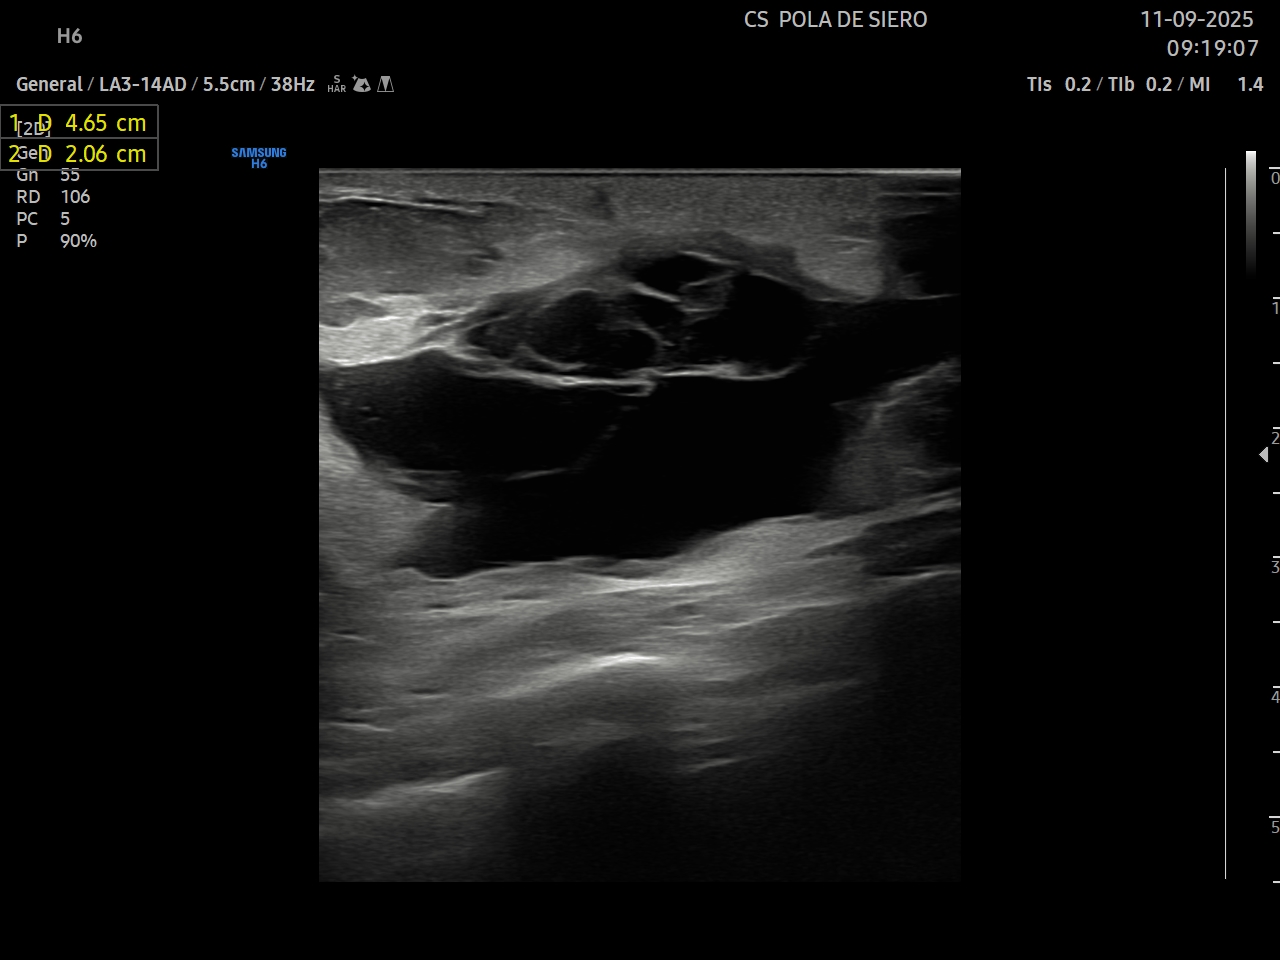

Ante la sospecha de infección local se realiza ecografía clínica para realizar diagnóstico diferencial entre celulitis y absceso de cara a un adecuado manejo del paciente.

Hallazgos ecográficos

Se identifica en el tejido celular subcutáneo una colección líquida, mal definida, de contornos irregulares, predominantemente hipoecoica con áreas ecogénicas en su interior. La lesión muestra refuerzo acústico posterior como corresponde a los contenidos líquidos. Con Doppler color presenta aumento de flujo periférico con escasa vascularización en su interior.

El diagnóstico diferencial se realizó entre celulitis y absceso. En este caso, fue diagnosticado de absceso en zona de la herida quirúrgica.